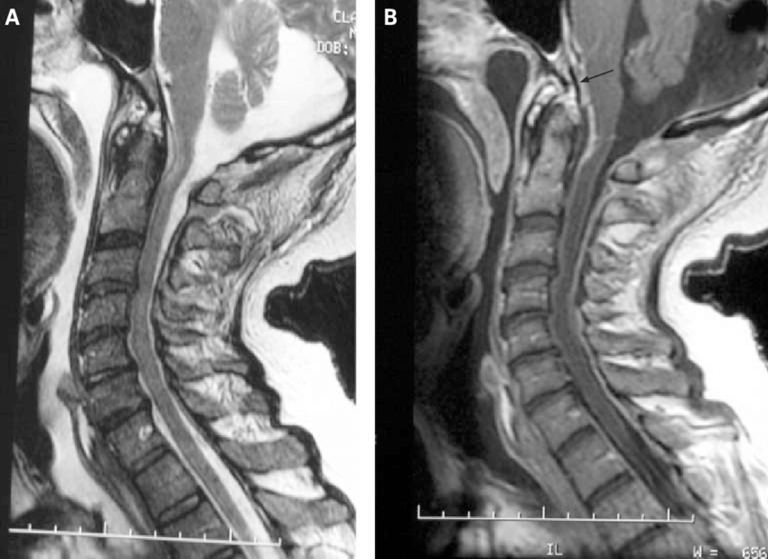

A 64-year-old man developed neck pain after falling off a truck one week ago. T1- and T2-weighted sagittal MR images (1 and 2) are provided. What are the findings? What is your diagnosis?

An extensive low signal intensity epidural abnormality posterior to the vertebral bodies and discs from C2 through C6 (arrows) produces spinal stenosis, most severe at C3, where there is resultant cord compression and faint T2 cord signal hyperintensity. Ossifications are present anterior to the vertebral bodies and discs (arrowheads).

ANSWER-

Ossification of the posterior longitudinal ligament (OPLL), continuous type, producing spinal stenosis, cord compression and edema. Diffuse idiopathic skeletal hyperostosis (DISH) is also present.